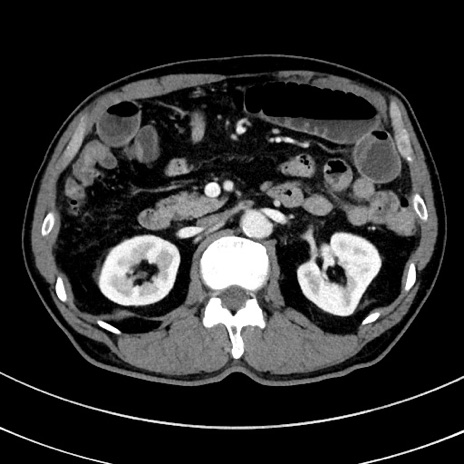

症例8(横断像)

【症例】 60歳代男性

【主訴】 黒色吐物

【現病歴】 4日前から嘔気自覚、2日前の朝食後にも嘔気あり、自分で手で嘔吐反射起こし嘔吐したところ血が混ざっていたため受診。

【既往歴】 5年前汎発性腹膜炎を伴う急性虫垂炎で手術、高血圧、前立腺肥大症、高脂血症

【身体所見】 腹部正中に手術癩痕あり 腹部平坦・軟圧痛なし膨満感あり

【データ】WBC 8400、CRP 4.54